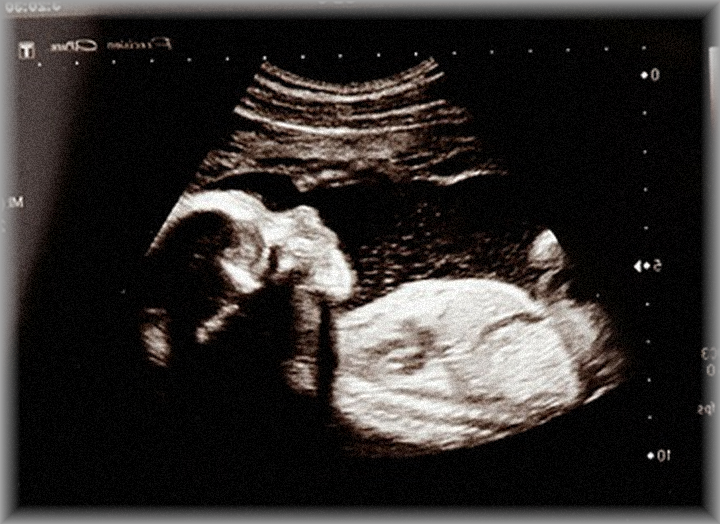

うちの嫁さん、現在妊娠5ヶ月です。

義兄嫁が今日産婦人科行ったら、

胎児が無脳症?で心臓もとまっていて、

明日手術で胎児を取り出すと連絡あり。